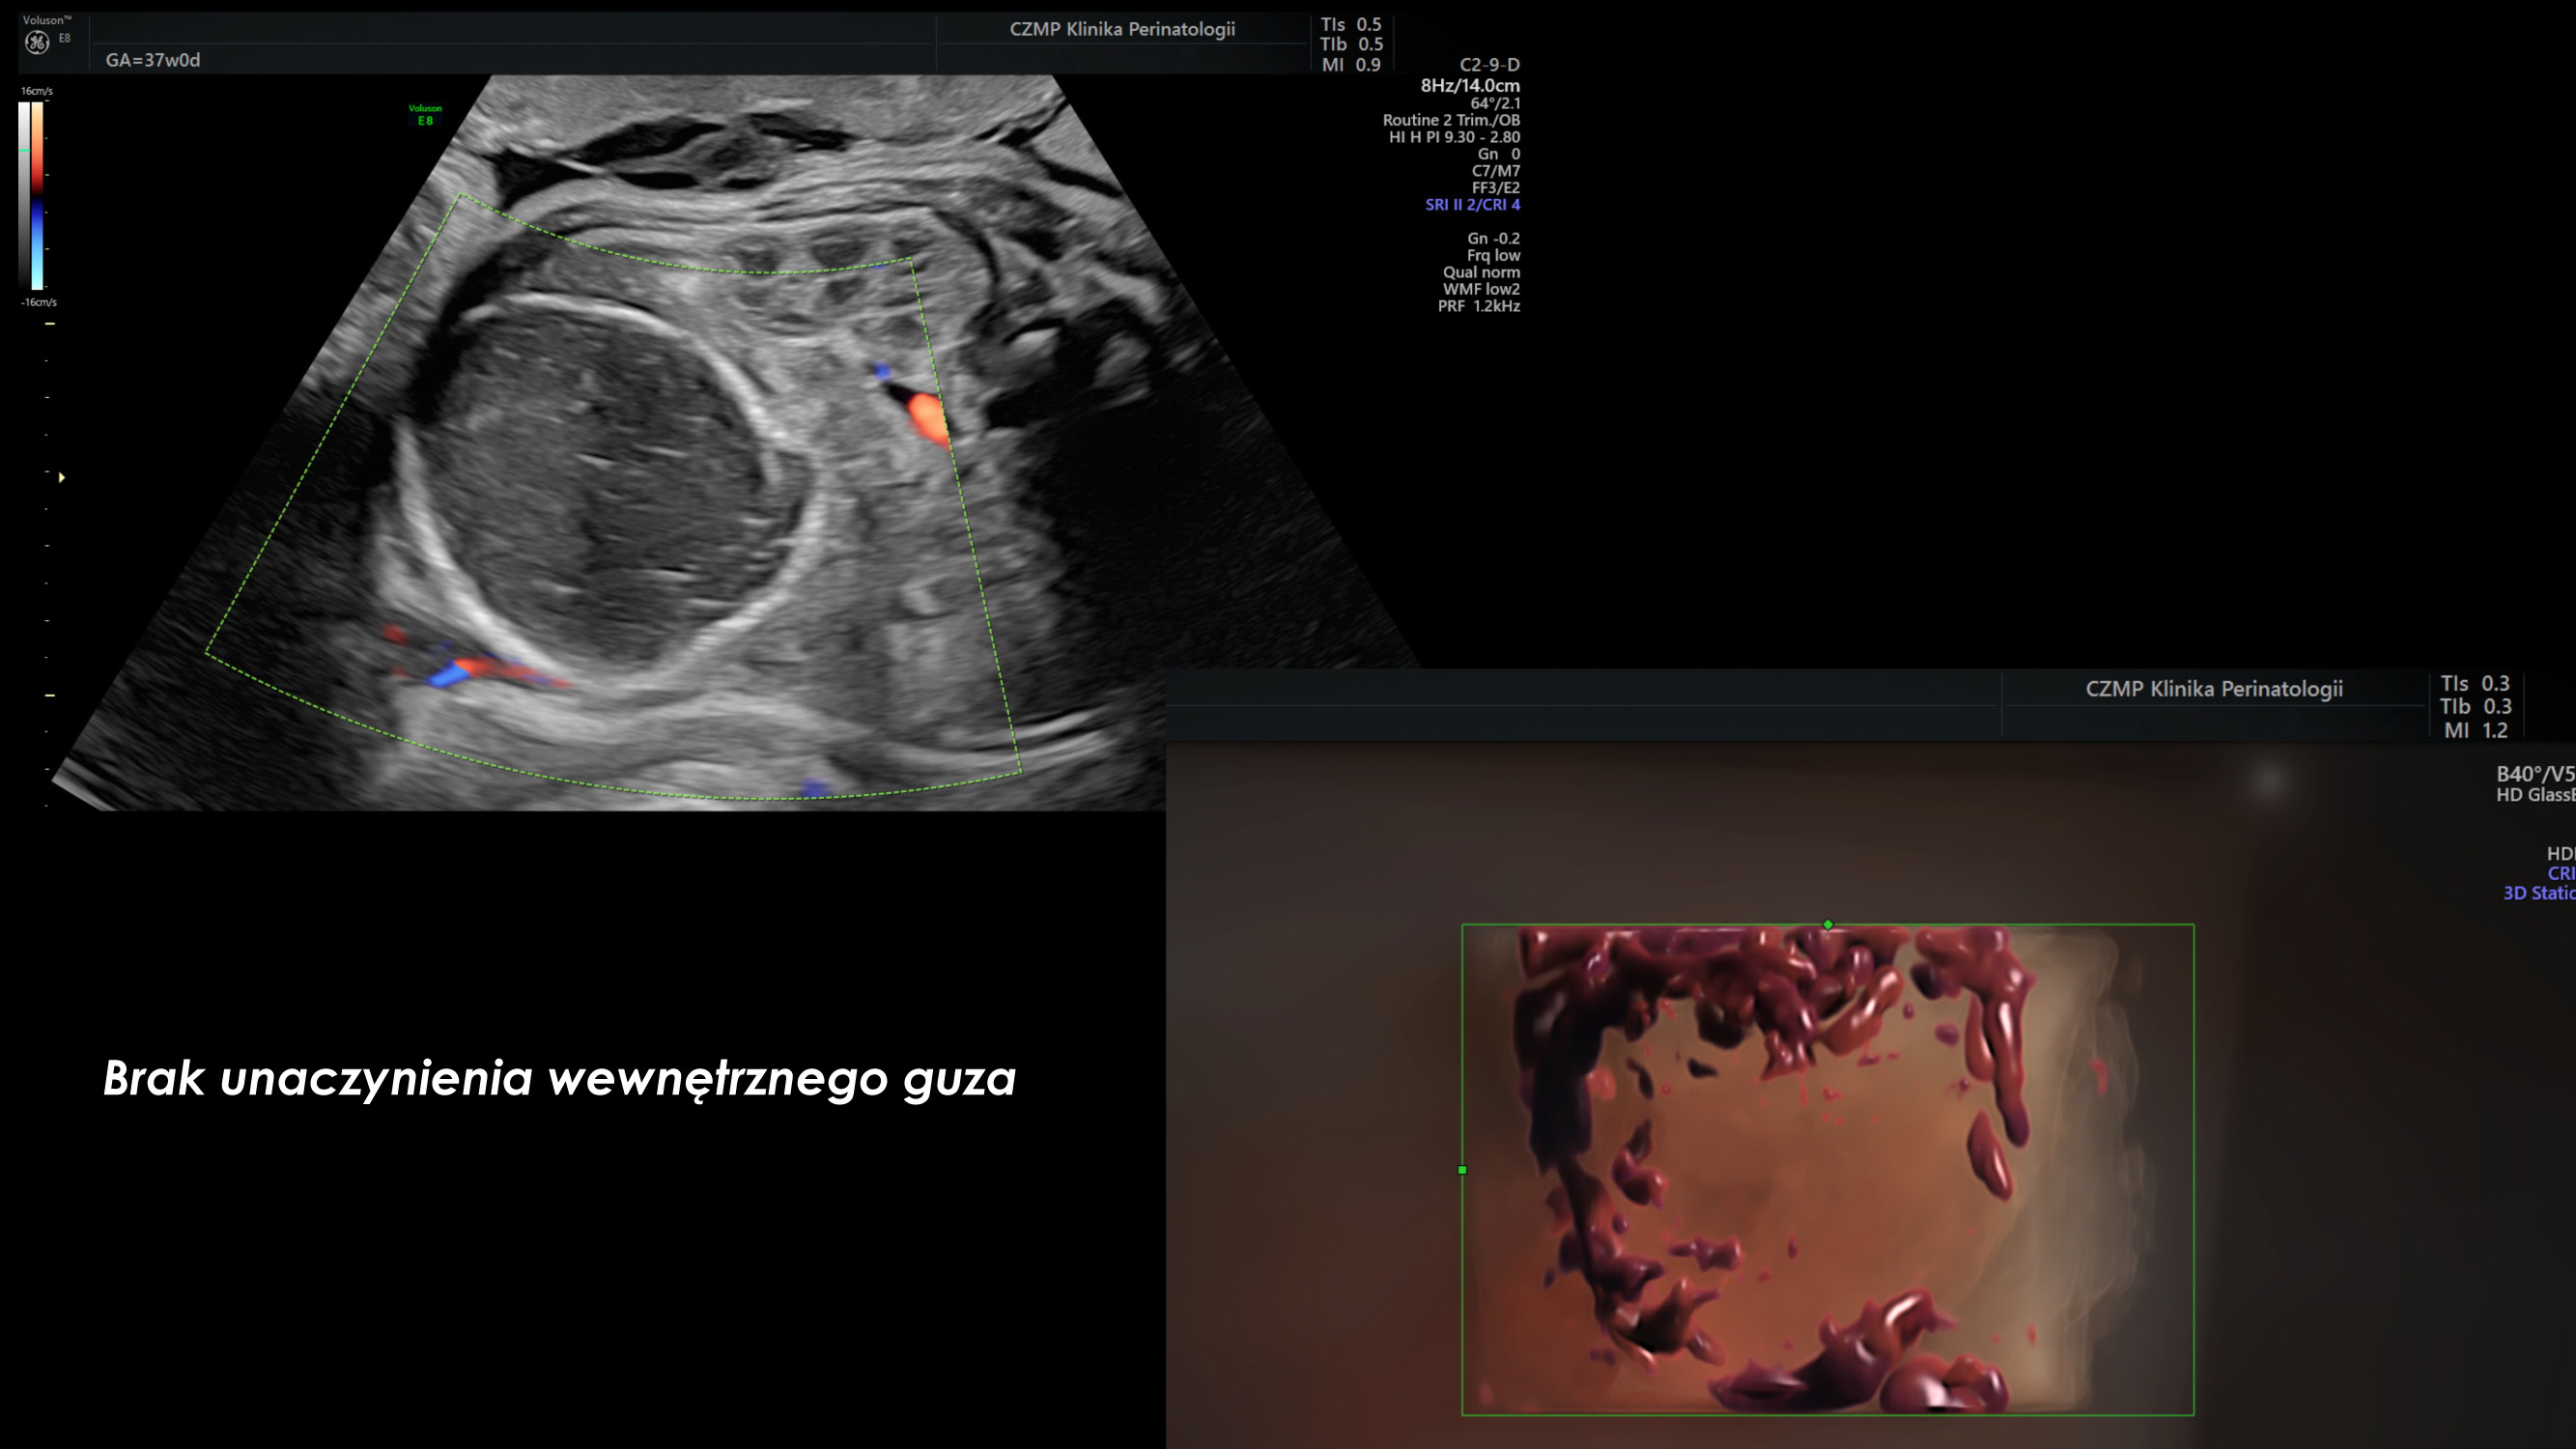

Nietypowy guz jamy brzusznej płodu